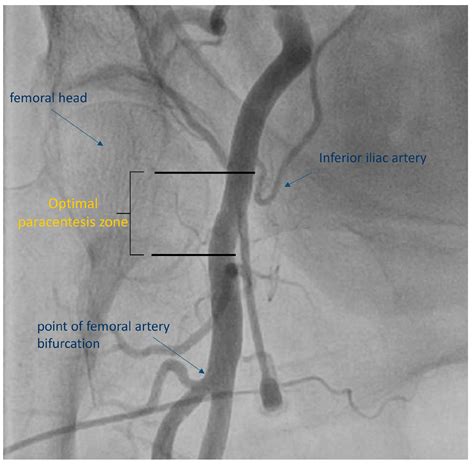

The superficial femoral artery is a critical component of the circulatory system. It originates from the common femoral artery in the groin area and travels down the thigh, passing through the adductor canal. This artery is particularly important because it provides blood flow to the muscles and tissues of the thigh, ensuring proper oxygenation and nutrient supply.

• The artery is located superficially in the thigh, making it accessible for various diagnostic and therapeutic procedures.

• It is surrounded by the femoral vein and nerve, forming the femoral triangle.

• The artery bifurcates into the profunda femoris artery and the superficial femoral artery.